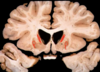

C = nucleo caudado P = Putamen S = nucleo estriado ## Footnote En la foto de abajo hay perdida del nucleo caudado. Comparar con la foto de arriba Ventriculos dilatados por perdida de masa encefalica = hidrocefalia ex vacuo

# Huntington El encéfalo es pequeño y muestra una atrofia llamativa del núcleo **...** y del **...**, componentes del cuerpo estriado posterior; el globo pálido puede atrofiarse secundariamente, y los ventrículos laterales y el tercer ventrículo están **...**

El encéfalo es pequeño y muestra una atrofia llamativa del núcleo **caudado** y del **putamen**, componentes del cuerpo estriado posterior; el globo pálido puede atrofiarse secundariamente, y los ventrículos laterales y el tercer ventrículo están **dilatados**

Figura 28.41 - Enf. de Huntington, hemisfério normal (izquierda) comparado con un hemisferio con **enfermedad de Huntington (derecha)** en el que se observa **atrofia del cuerpo estriado y dilatación ventricular**. Recuadro. Inclusiones intranucleares en las neuronas destacadas mediante tinción inmunohistoquímica para ubicuitina